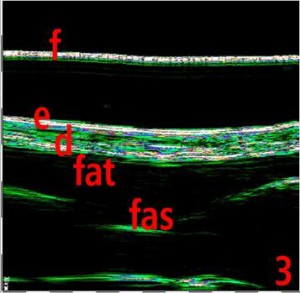

-Υπέρηχος Υψηλής Συχνότητας (HFUS) και Ιστολογία

Εφαρμογές δερματολογίας

-Κύριες εφαρμογές

-Κύριες παθολογικές διεργασίες